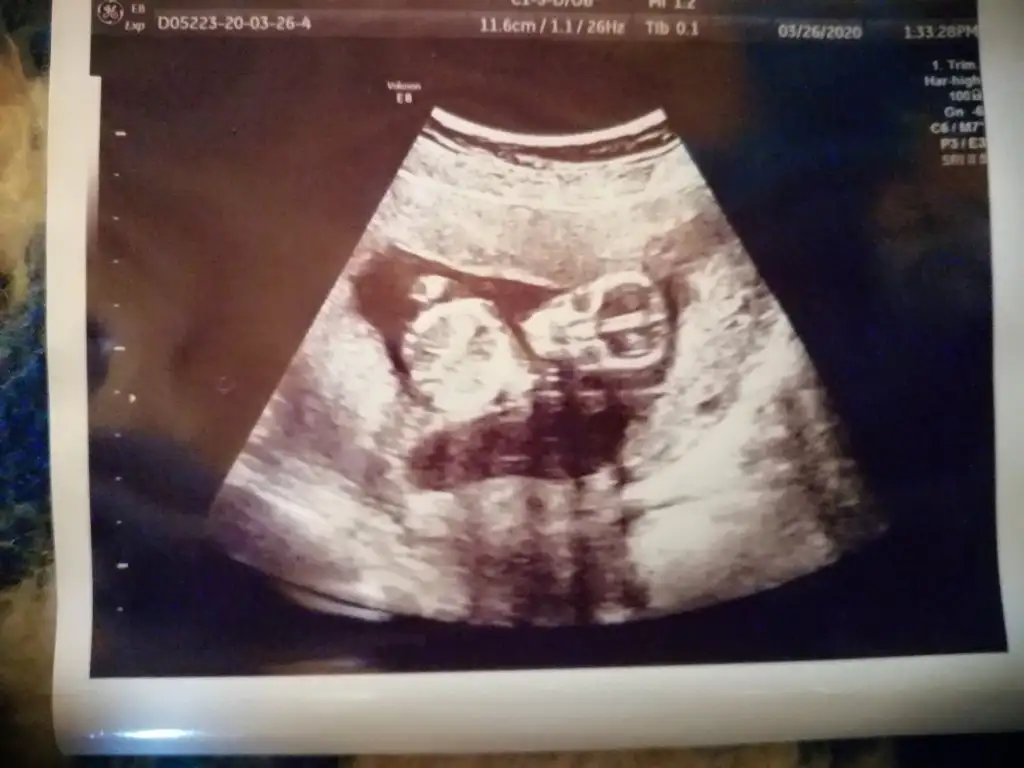

dr soylemeden siz gorun genital nub teorisi ( bebegin cinsiyeti)

Canımlar biliyorum biraz büyüdü bebegim ama yinede yorum yaparmisiniz

Bugün kontrole gittim doktor bacaklarını açmıyor cinsiyet göremedim dedim ikra meyra sen erkek demistin hep ama bitek bu foto var 14 haftalik bu arada yine varmi tahmin

ay bende çok merak ediyorum 14haftalık usg bu acaba kız mı erkek mi olacak 😊 doktor bacaklarını açmıyor dedi 2 hafta sonrada çağırdı kesin Konuşuruz dedi ama ben duramıyorum meraktan

Nubu net değil sanki erkek gibi bilemedim ben 11 12 13 haftalara bakıyorum 14 de organı oluşuyor çunki